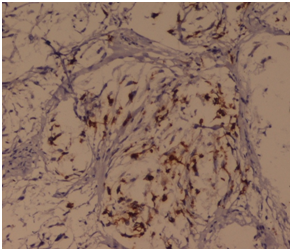

Figure 4 On Immunohistochemistry, the foci of nerve proliferation showed diffuse positivity with S100. IHC S 100 x 40X.